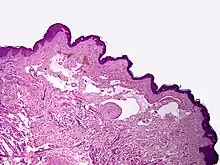

Microscopically, the vesicles in lymphangioma circumscriptum are greatly dilated lymph channels that cause the papillary dermis to expand. They may be associated with acanthosis and hyperkeratosis. There are many channels in the upper dermis which often extend to the subcutis (the deeper layer of the dermis, containing mostly fat and connective tissue). The deeper vessels have large calibers with thick walls which contain smooth muscle. The lumen is filled with lymphatic fluid, but often contains red blood cells, lymphocytes, macrophages, and neutrophils. The channels are lined with flat endothelial cells. The interstitium has many lymphoid cells and shows evidence of fibroplasia (the formation of fibrous tissue). Nodules (A small mass of tissue or aggregation of cells) in cavernous lymphangioma are large, irregular channels in the reticular dermis and subcutaneous tissue that are lined by a single layer of endothelial cells. Also an incomplete layer of smooth muscle also lines the walls of these channels. The stroma consists of loose connective tissue with a lot of inflammatory cells. These tumors usually penetrate muscle. Cystic hygroma is indistinguishable from cavernous lymphangiomas on histology.[4]

Cystic hygroma causes deep subcutaneous cystic swelling, usually in the axilla, base of the neck, or groin, and is typically noticed soon after birth. If the lesions are drained, they will rapidly fill back up with fluid. The lesions will grow and increase to a larger size if they are not completely removed in surgery.[4]